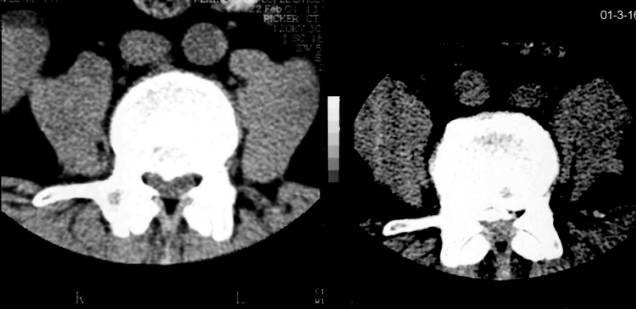

3、CT检查:可取之处在于可准确显示异常组织的性质,直接显示椎间盘突出的真实性质和范围。可清楚地显示椎管横断面的骨性结构,对侧隐窝狭窄,黄韧带肥厚,椎间关节病变及神经孔周围极外型椎间盘突出的显示有独特的临床价值。

但此检查不足之处在于对软组织分辨率低,不能直接进行矢状面、斜面扫描。对纤维环膨出显示较模糊,有假阳性情况。

椎体后方静脉孔处的骨质间隔,不要误认为后纵韧带骨化

椎管狭窄并间盘突出

椎管狭窄

中央性椎管狭窄

侧隐窝狭窄